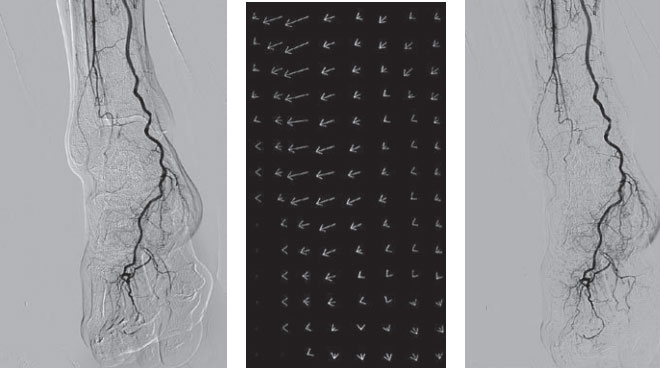

Flex-APS技术,将蒙片像与实时图像之间的变动作为运动矢量,利用每一像素、每一帧计算得出,基于此矢量,在对蒙片像进行了非线性变换后,进行计算,即可对扭曲、弯曲、部分身体移动进行校正。因此,即使用传统的像素偏移处理不能够处理的身体晃动,也能够得到经过充分校正的DSA图像。由于校正处理是实时进行的,因此摄影过程中,所有显示的图像都是通过Flex-APS校正后的DSA 图像。

Flex APS操作非常简单,床旁即可实现。只需在造影前选定Flex-APS模式,便可以自动进行该处理,实时去除因患者体动而引起的图像扭曲,医师可以专注于手术。无需繁琐的图像后处理,大大提高工作效率。能够应对伴随扭曲的体动,无需重新拍摄,减少被辐射剂量和造影剂,是外周介入的强大助力。